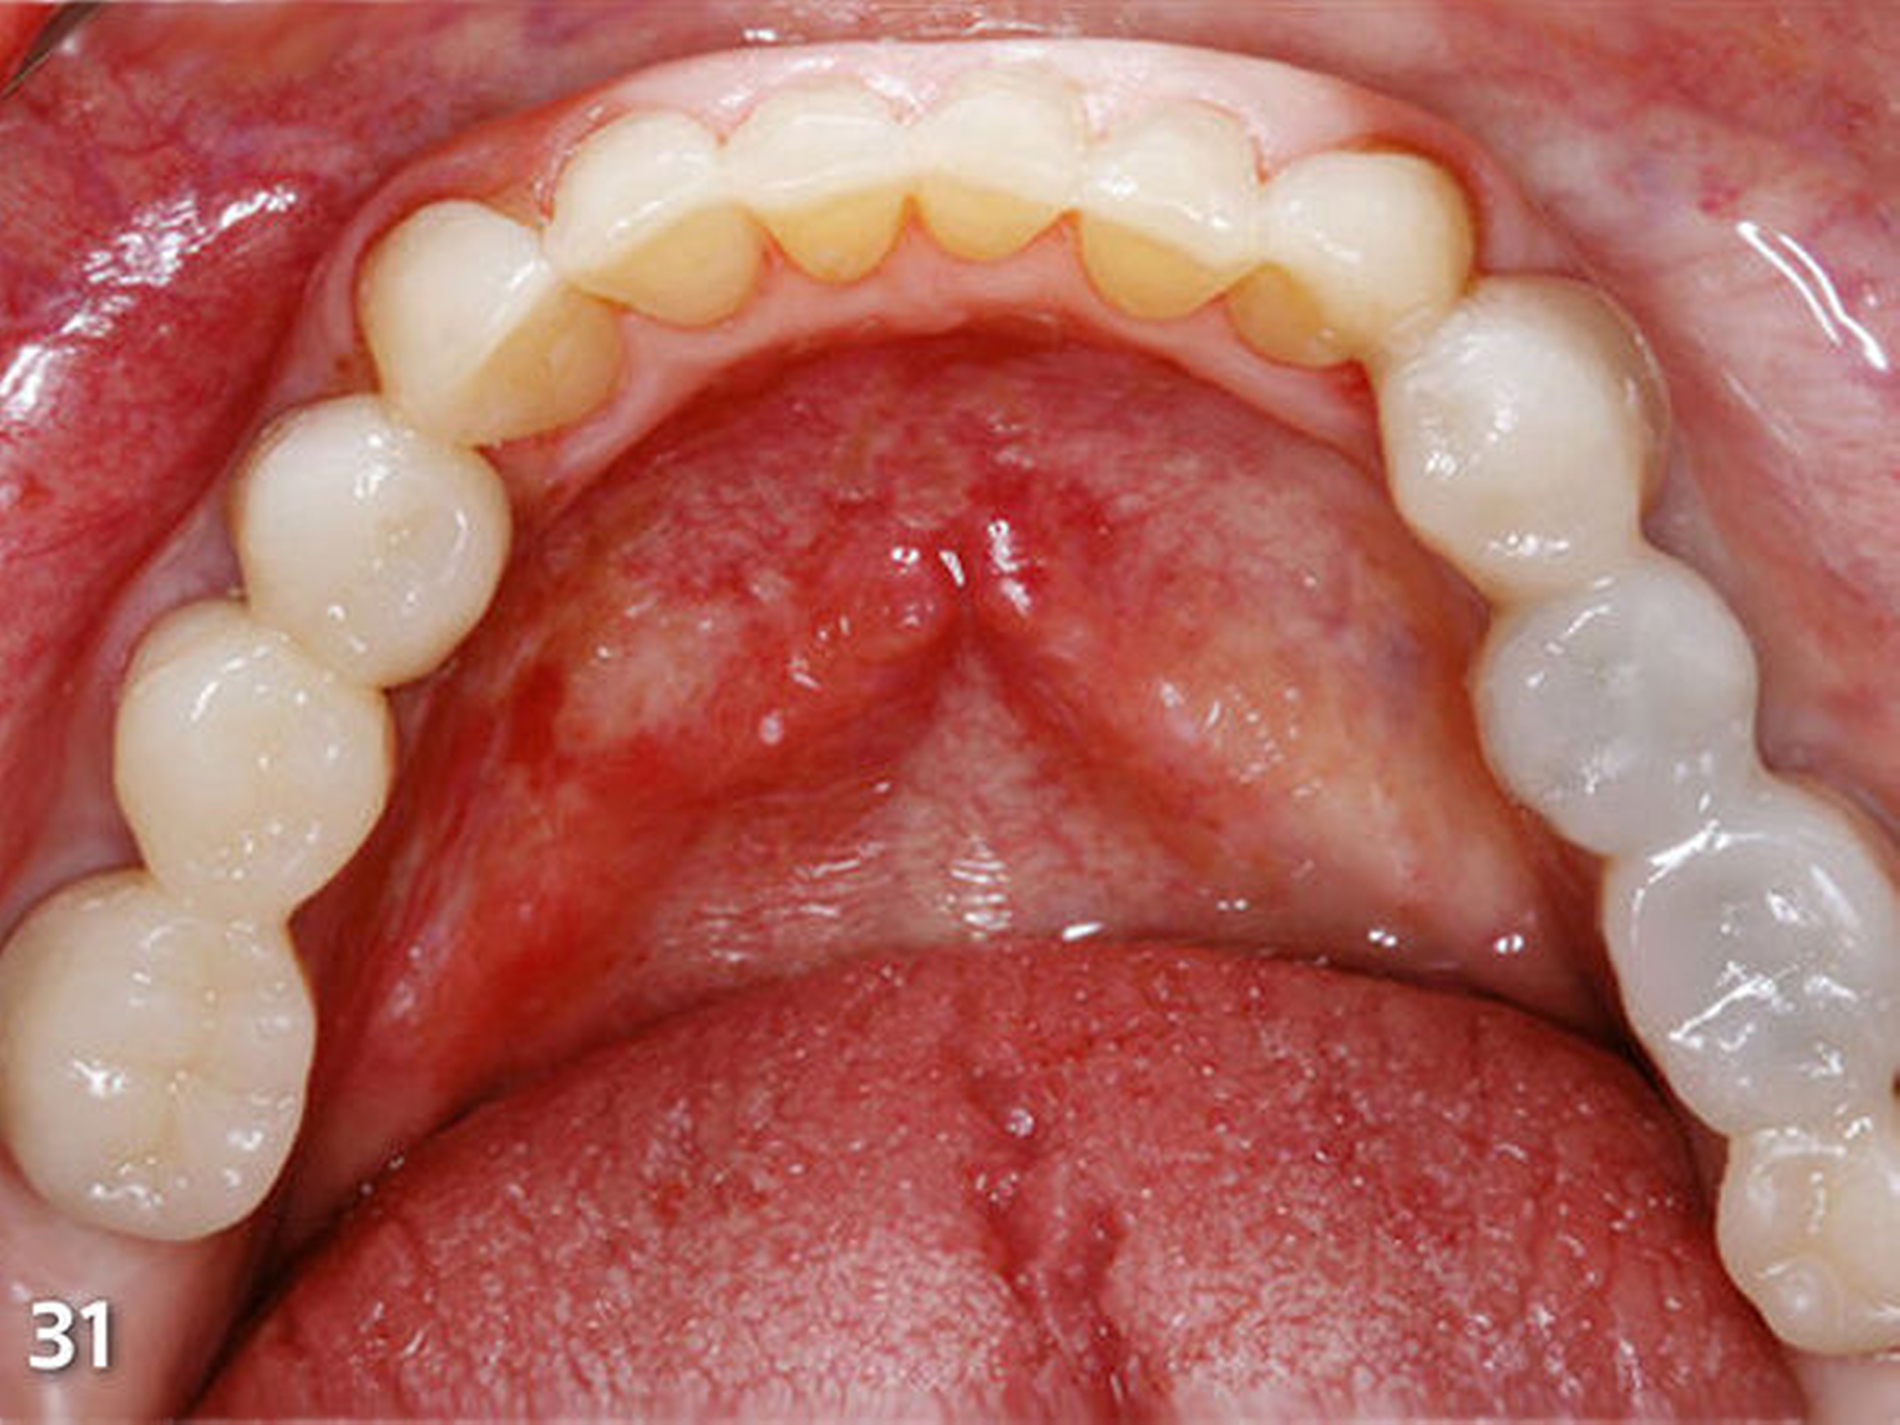

Nach dem Ausarbeiten und Polieren sämtlicher Restaurationen (Abb.31 und 32) wurden die statische und die dynamische Okklusion nochmals kontrolliert; es zeigte sich eine gute Übereinstimmung mit dem okklusalen Kontaktmuster aus dem Wax-up (Abb.33). Da sämtliche Restaurationen ohne Verabreichung von Lokalanästhesie aufgebaut wurden, konnte die Patientin sofort nach Abschluss der Behandlung, nach einer kurzen Phase der Lockerung der Kaumuskulatur, ein erstes positives Feedback zur neuen Unterkieferposition geben (Abb.34 und 35).